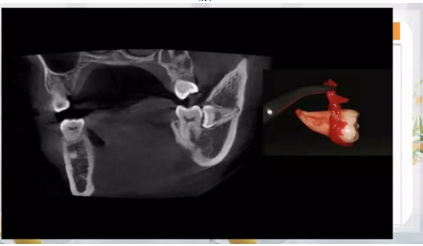

阻生齒外科聯(lián)合正畸治療

24.png